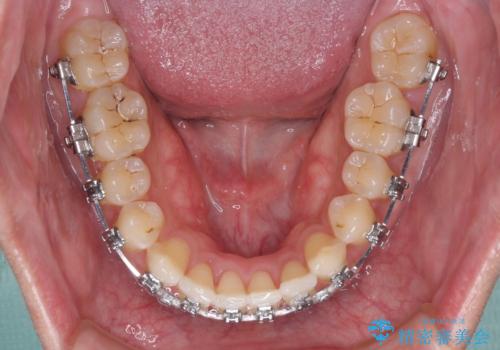

- メタルブラケット

- 1年4ヶ月

- 前歯のデコボコを気にして来院された患者様です。

インビザラインによるマウスピース矯正も適用となる歯列でしたが、できる限り自己管理の煩わしさのない状態で治したいとのことで、ワイヤー装置にて矯正治療を行うこととしました。